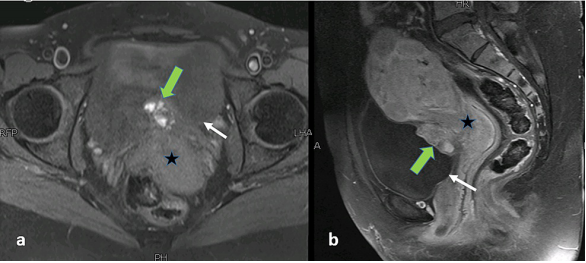

骨盆MRI显示增大的子宫,有多个子宫肌瘤和沿膀胱后壁的不规则混合信号强度肿块。该病变表现为膀胱内延伸,向后与子宫接触,脂肪平面不明显(图2)。经仔细检查,发现该病变引起了可能侵犯肌肉的外在印象。它的颅尾、AP和横向尺寸为36 x 29 x 21 mm,外观提示膀胱生长。然而,该病变的信号特征是出血性病变的典型特征,在T2加权序列上返回异质性低信号(图2),T1加权序列上的异质高信号,伴有斑片状对比增强(图2)(图3)和焦点扩散限制(图4)。鉴于患者的病史,MRI检查结果与膀胱子宫内膜异位症一致。

图3. 骨盆MRI图像。(a)轴向T1加权脂肪饱和图像显示沿膀胱底部(白色箭头)边界不清的不均匀高信号病变(绿色箭头)。(b) 矢状面造影后T1加权脂肪饱和图像显示病变内的斑片状增强(绿色箭头)